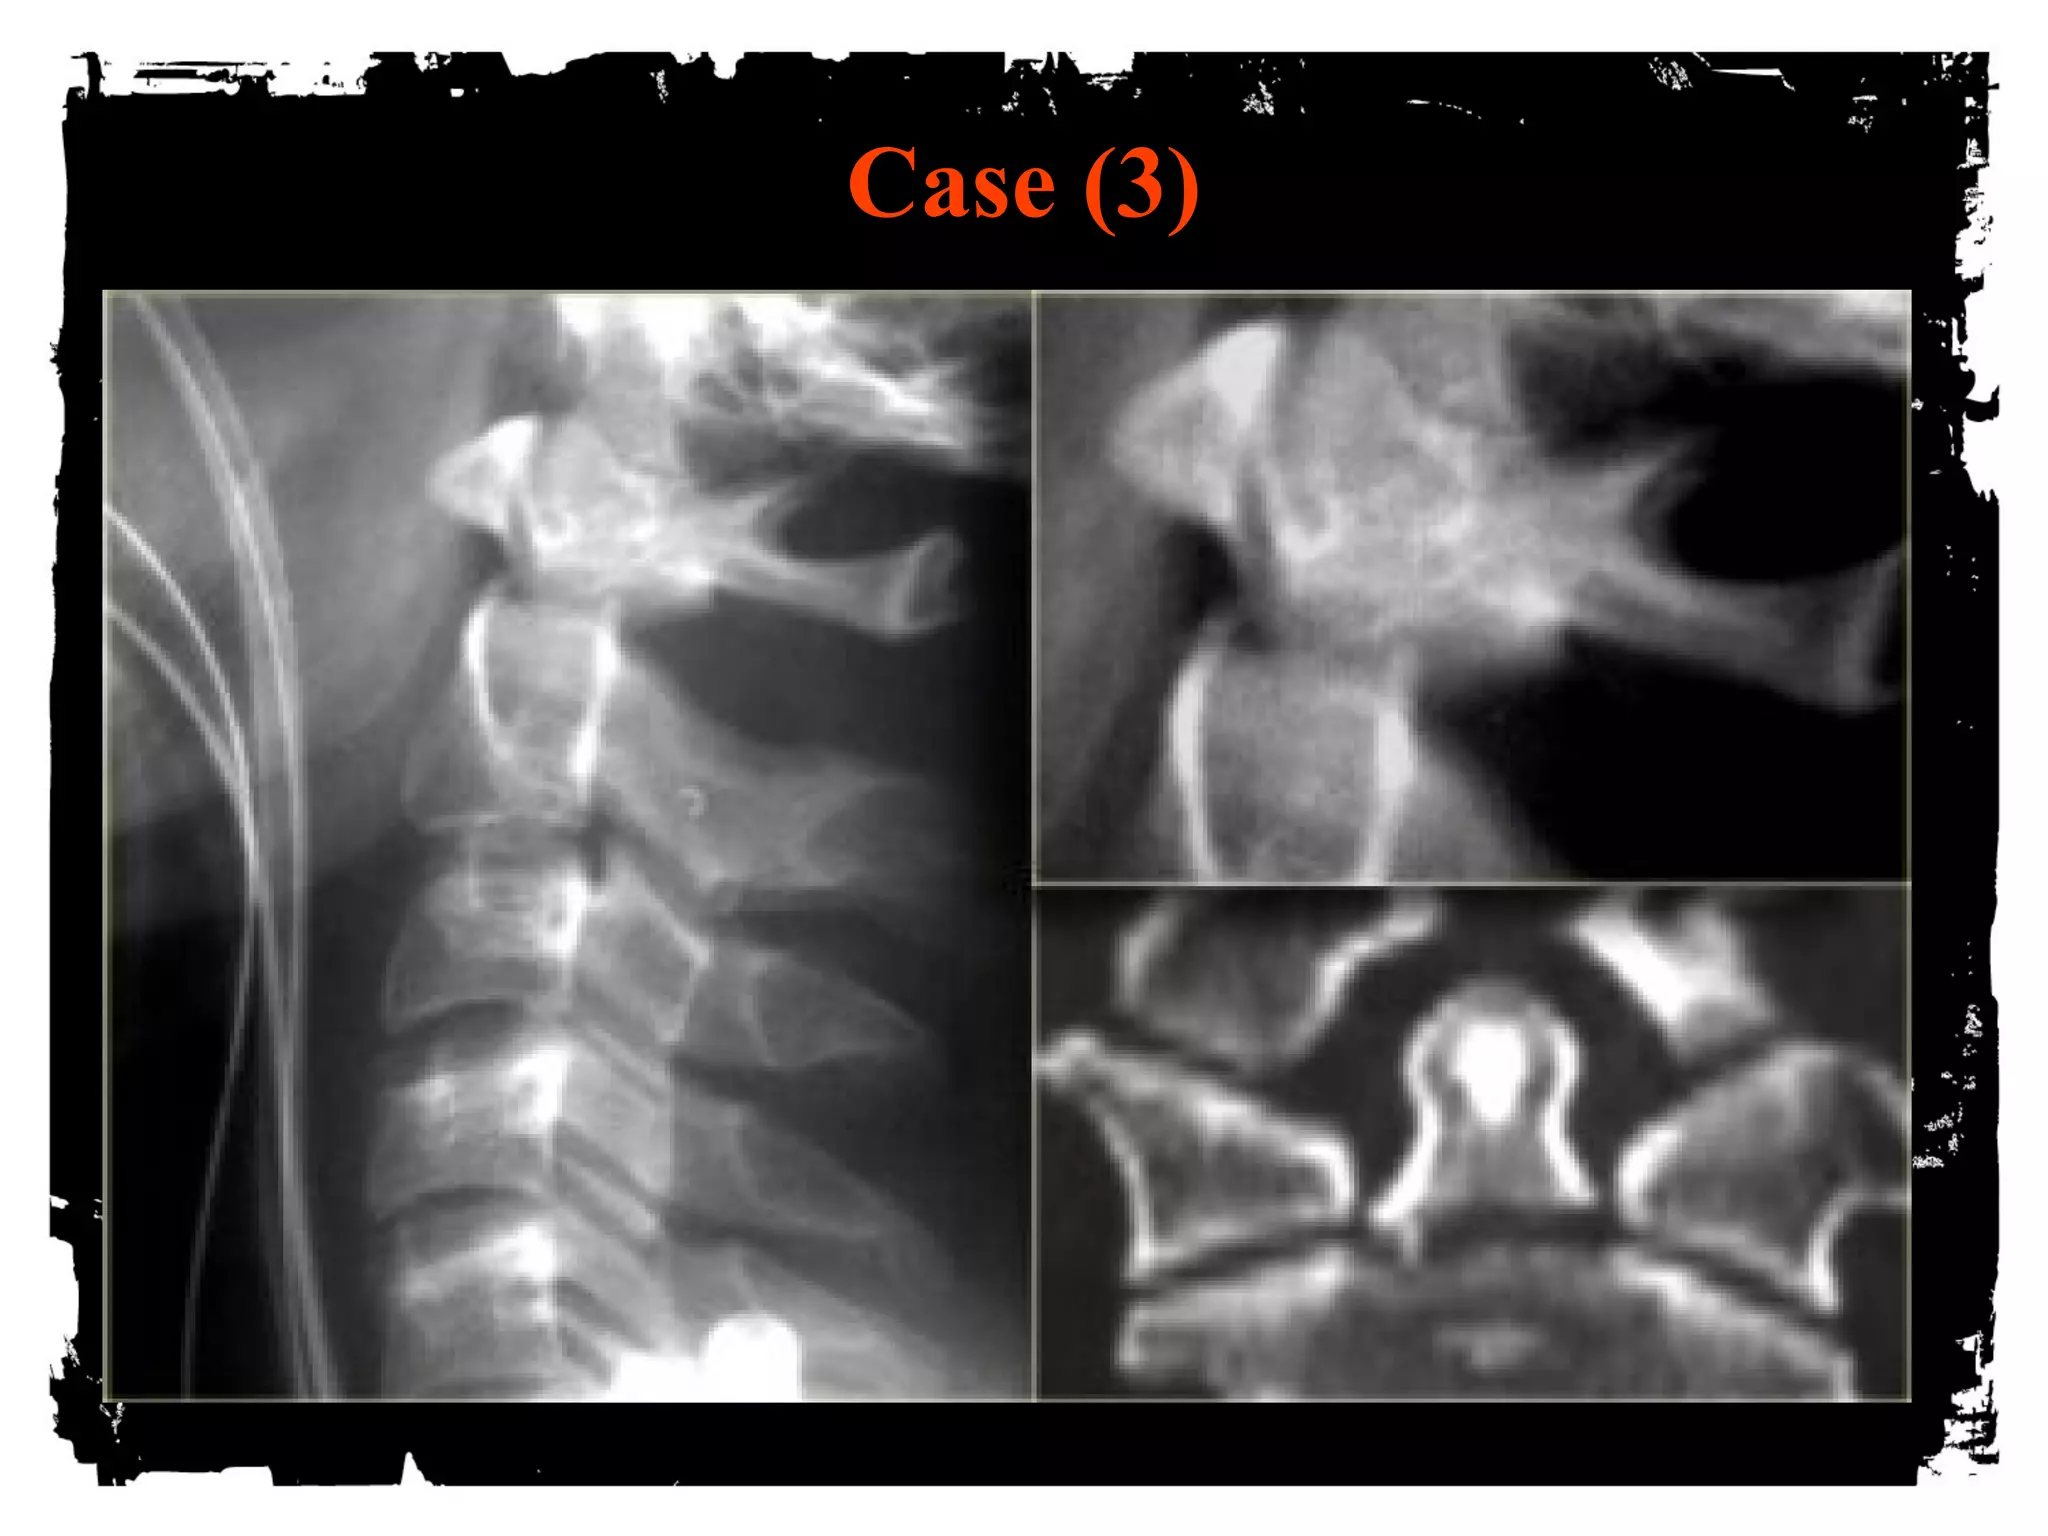

Case (3)

Case (4)

Flexion Tear Drop

Flexion+compression (MVA)

Teardrop fragment comes from the anteroinferior

aspect of the vertebral body

Larger posterior part displaced backward into the

spinal canal

Facets joints and interspinous distances usually

widened, disk space may be narrowed

70% of patients with neurologic injuries

Unstable fracture (complete disruption of ligaments

and anterior cord syndrome